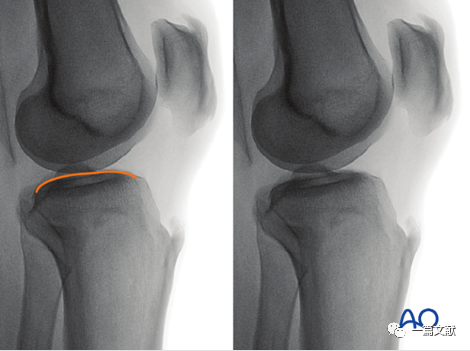

四,改良侧位片评估外侧平台关节面

1)体位:在标准侧位基础上,将患肢外展10°-20°。如下图:

2)此标准位片的评估:1、稍突起的外侧平台关节面位于呈凹陷状的内侧关节面的头端;2、外侧胫骨平台面位于图像中央。如下图:

3)解剖标志的识别:如下图:凸起关节线为外侧胫骨平台。

4)此位片的意义:1、评估外侧平台关节面情况;2、检视是否有内固定穿透外侧平台。

五,改良侧位片评估内侧平台关节面

1)体位:在标准侧位基础上,将患肢内收10°-20°。如下图:

2)此标准位片的评估:1、稍凹陷的内侧平台关节面位于呈凸起状的外侧平台关节面的头端;2、内侧胫骨平台面位于图像中央。如下图:

3)解剖标志的识别:如下图:凹陷的关节线为内侧胫骨平台。

4)此位片的意义:1、评估内侧平台关节面情况;2、检视是否有内固定穿透内侧平台。